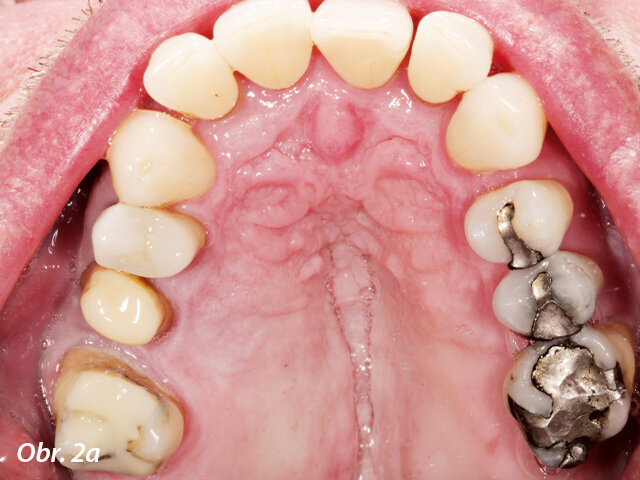

Pacient požadoval výměnu amalgámových výplní v horní (a) a dolní (b) čelisti za celokeramické náhrady.

Pacient si přál odstranit víceploškové amalgámové výplně v horní a dolní čelisti (obr. 2a, b) a nahradit je celokeramickými náhradami zhotovenými s co nejmenším úsilím. Jednalo se o částečné korunky. V distálním úseku horní čelisti byla indikována můstková náhrada vyrobená z lithium disilikátové keramiky. Všechny ostatní nepřímé náhrady měly být vyrobeny z materiálu n!ce. Materiál je biologicky kompatibilní a relativně pevný i bez dodatečného krystalizačního pálení, přičemž disponuje přirozenými světelně optickými vlastnostmi.